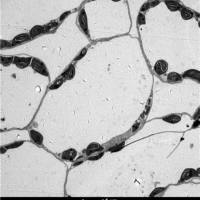

文献和实验一、石蜡切片和冰冻切片的比较? 1、要求做冰冻切片的不一定能做石蜡切片,这是我向一老师请教得出的结论。因为作石蜡切片时要高温烤片,可能会破坏组织的抗原性,如果组织的抗原性较稳定,则可作石蜡切片;但是要求做石蜡切片的,可作冰冻切片。 2、冰冻切片的优点是能够较好的保存组织的抗原免疫活性,做免疫组化时不需抗原修复这一步。缺点是细胞内易形成冰晶而破坏细胞结构,可能会使抗原弥散;切片厚度较石蜡的厚,做的片子没石蜡的漂亮。当你买一抗时,目录上都写着做什么样的切片,如果它写着只能做冰冻,就不能做石蜡,如写